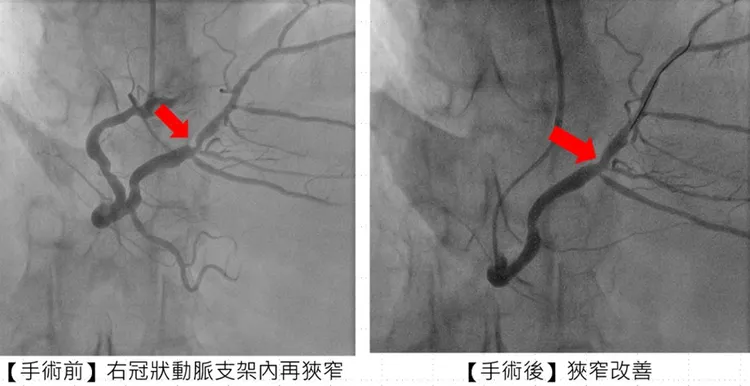

針對從花蓮遠道而來的張姓患者治療過程,市醫副院長兼心臟科專家陳建鈞醫師進一步說明,病人有多次支架再阻塞的病史,加上長途奔波與生活壓力,病情更加複雜。經團隊縝密評估後,決定採用「刀片氣球」及「塗藥氣球」治療,既能打通血管阻塞,也可降低再度狹窄的風險,大幅縮短康復時間。手術全程順利,患者隔日即可出院,術後更能安心規劃生活與健康管理。

張姓患者手術前後的情況。市醫提供